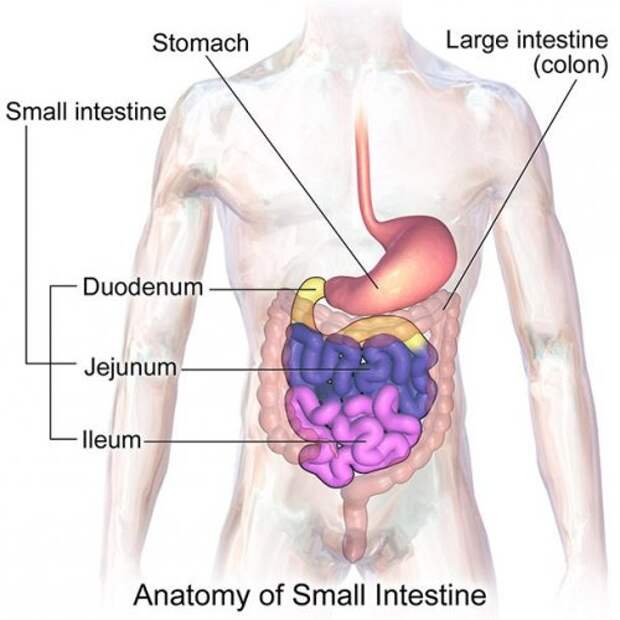

21. Тонкая кишка человека состоит из трех отделов – из двенадцатиперстной кишки, тощей кишки и подвздошной кишки.

Фото: BruceBlaus

21. Тонкая кишка человека состоит из трех отделов – из двенадцатиперстной кишки, тощей кишки и подвздошной кишки.

Фото: BruceBlaus